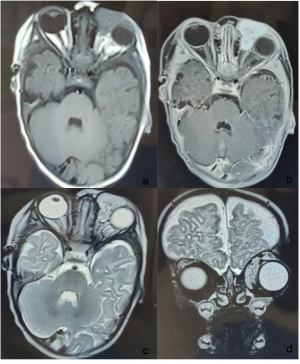

Infantile Haemangioma. a & b) CE MRI (T1 weighted) of brain and orbit- Axial section showing well-defined lesion involving the left orbit with no intraconal extension, involving the medial rectus muscle. It shows heterogeneous enhancement with contrast. c & d) MRI brain and orbit (T2 weighted)- Axial and coronal section, the lesion shows hyperintensity. | |